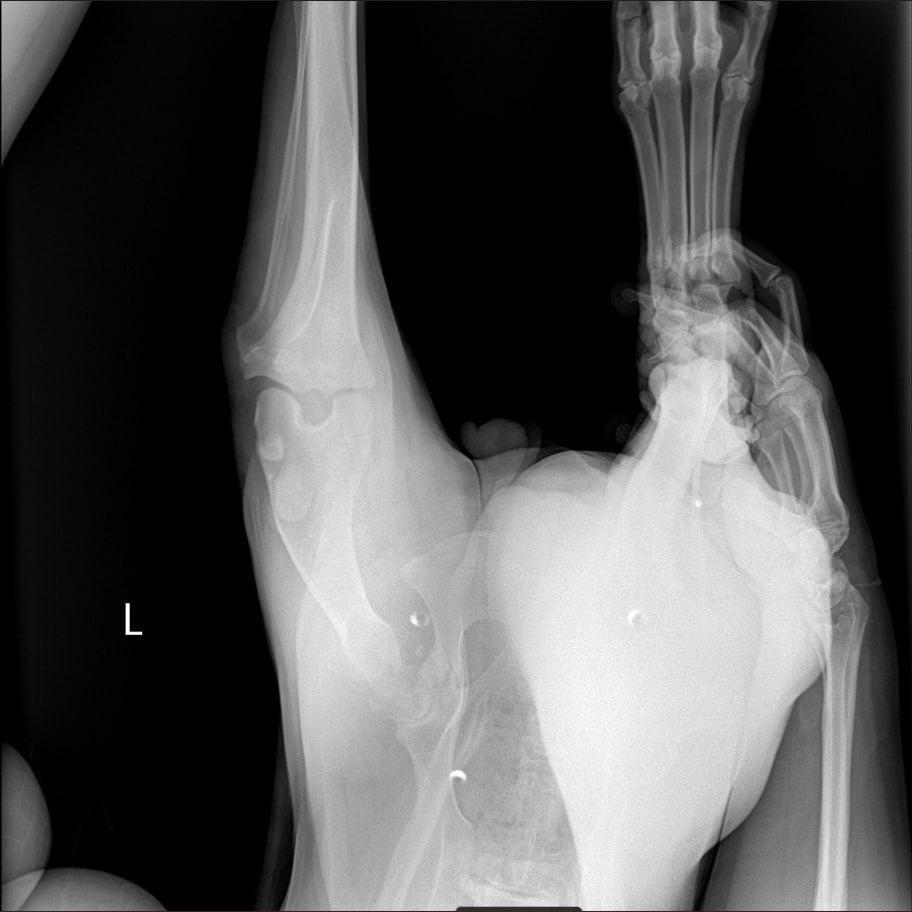

Рентген лапы, которая болит

Зона операции в снимок не попала....но со слов врача все нормально. То что видно - чисто....придется поверить, но так как шов подтекает, антиюиотик попробуем заменить на клиндомицин.

Сильнейший коксартроз тбс на больной лапе.....который не заметили на первичных осмотрах....зато настаивали в необходимости кастрации. В результате изменения положения лапы, нагрузки - воспаление и боль.